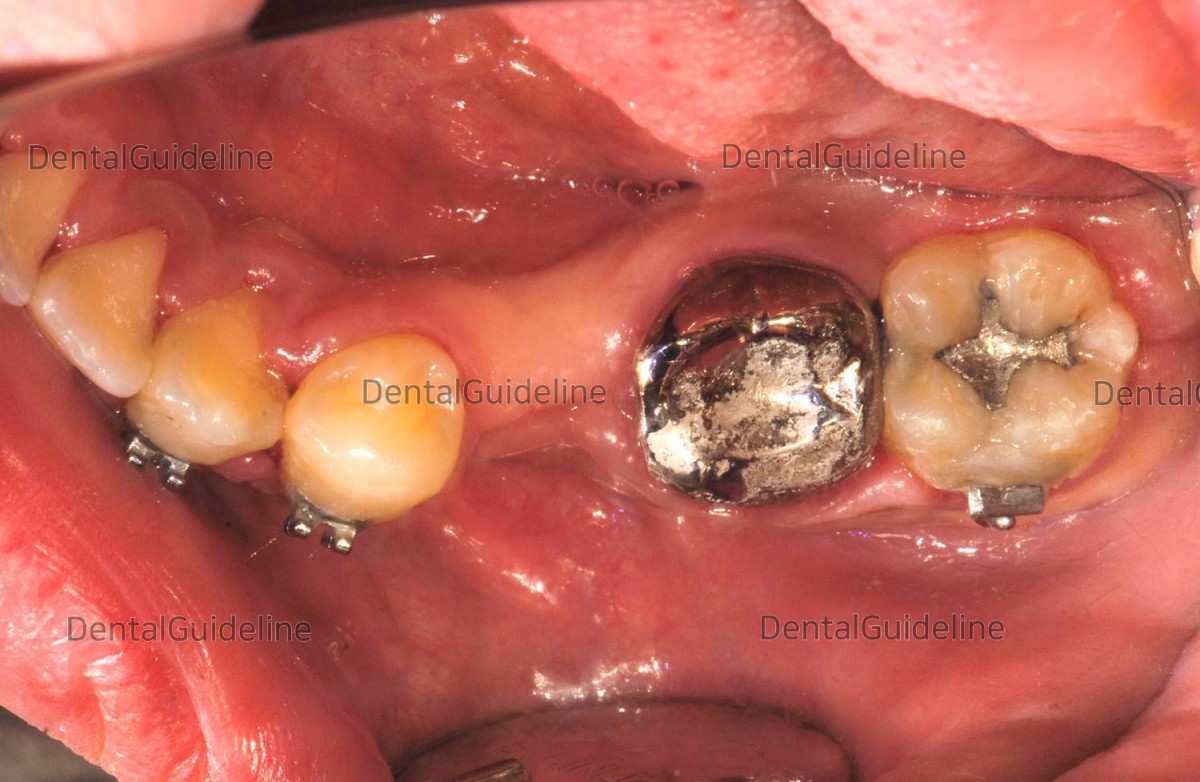

Distal tipping of the premolar due to the area of the missing tooth.